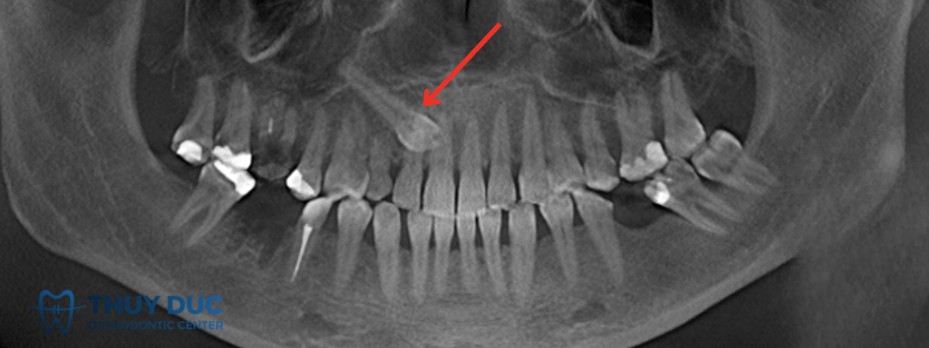

Vì vậy, phương pháp chẩn đoán chính xác nhất là chụp X-quang (thường là phim panorama hoặc phim cận chóp). Trên thực tế, rất nhiều bệnh nhân chỉ phát hiện mình có răng mọc ngầm khi đi khám và chụp phim để điều trị một vấn đề khác, ví dụ sâu răng, viêm nha chu hoặc chuẩn bị niềng răng.

2.2 Răng nanh mọc ngầm

Răng nanh giữ vai trò quan trọng trong thẩm mỹ và định hướng khớp cắn. Răng nanh vĩnh viễn mọc ngầm thường gặp ở hàm trên và có thể gây chen chúc, sai lệch khớp cắn nếu không được phát hiện sớm. Điều trị thường kết hợp phẫu thuật bộc lộ và kéo răng bằng khí cụ chỉnh nha.